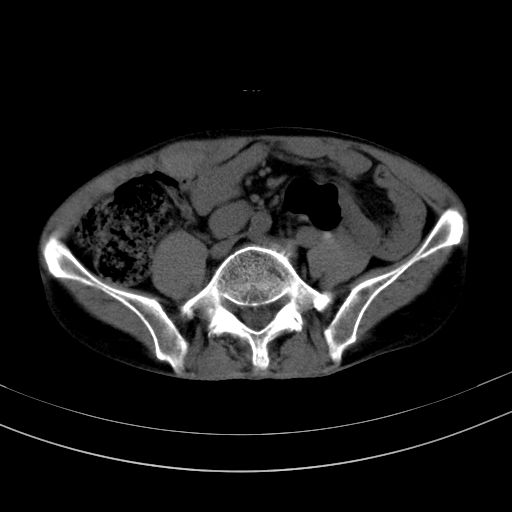

以下是引用37度在2010-1-9 14:37:00的发言:[br]1.双肾囊肿,左肾积水结石,.胆总管轻度扩张;[br]2.病灶在腹膜外,考虑纤维瘤。

以下是引用dyqct在2010-1-9 17:56:00的发言:[br]考虑:1.双肾囊肿,左肾积水结石、旋转不良。[br] 2.右侧腹直肌血肿或纤维瘤。[br]肠道准备不好。做个增强。